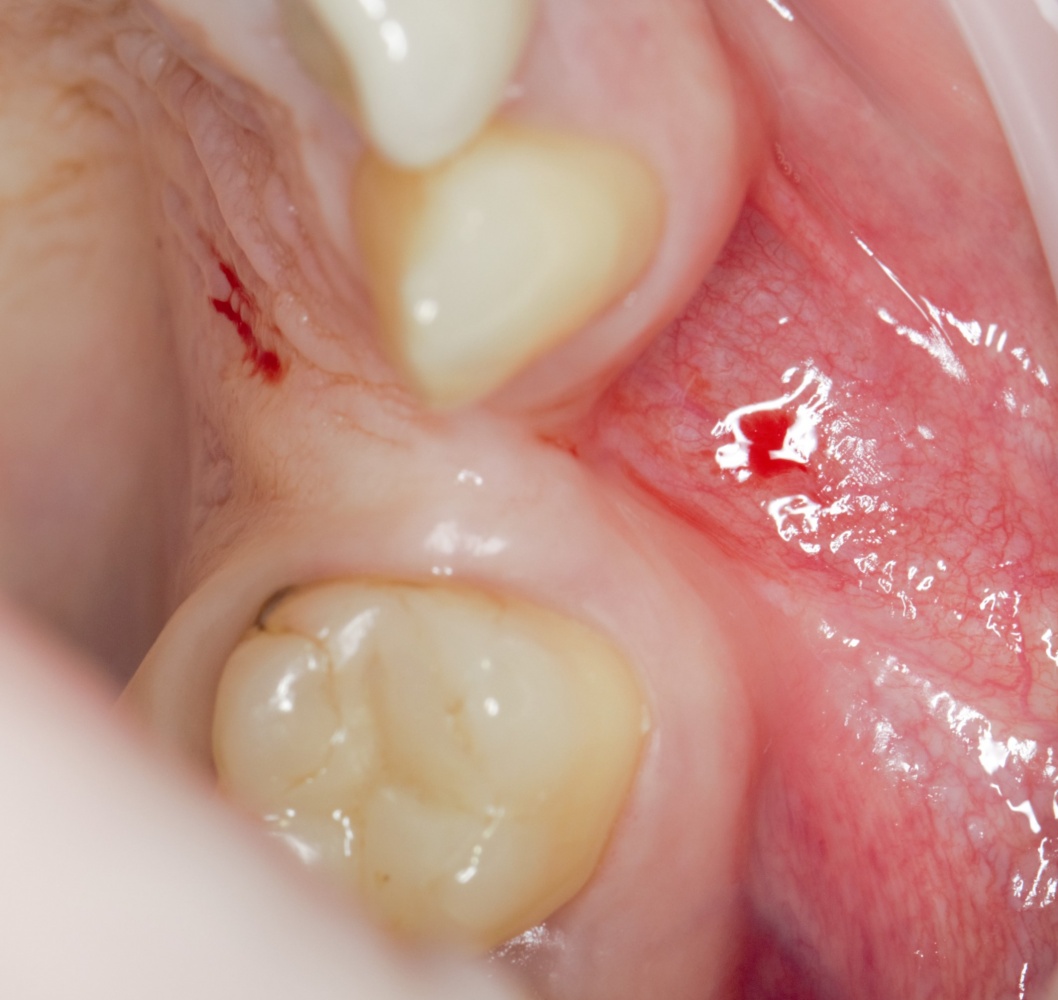

Простой. Надежный. Дешевый. Способ остеопластики.